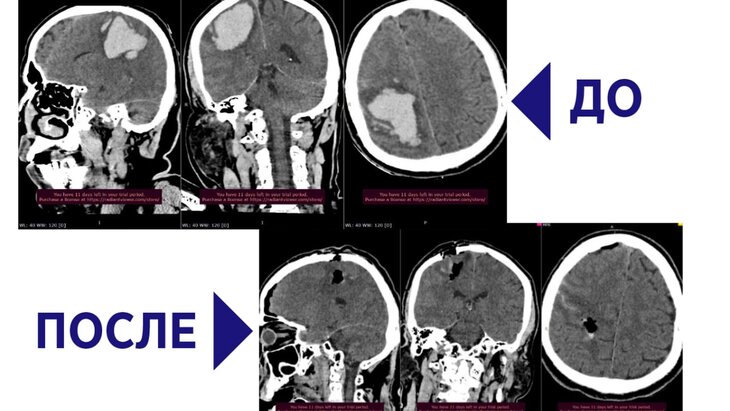

Фото: ГБУЗ МО "Сергиево-Посадская больница"

Доставленный бригадой скорой помощи 56-летний мужчина находился в коме. По итогам КТ-исследования врачи обнаружили внутримозговую гематому объемом около 70 миллилитров, которая образовалась в результате геморрагического инсульта.

Пациента экстренно направили на операцию, в ходе которой хирурги аккуратно и последовательно извлекли из мозга все кровяные сгустки при помощи аспиратора. Спустя несколько часов после вмешательства мужчина пришел в сознание. Постепенно к нему вернулись речевые и двигательные функции.